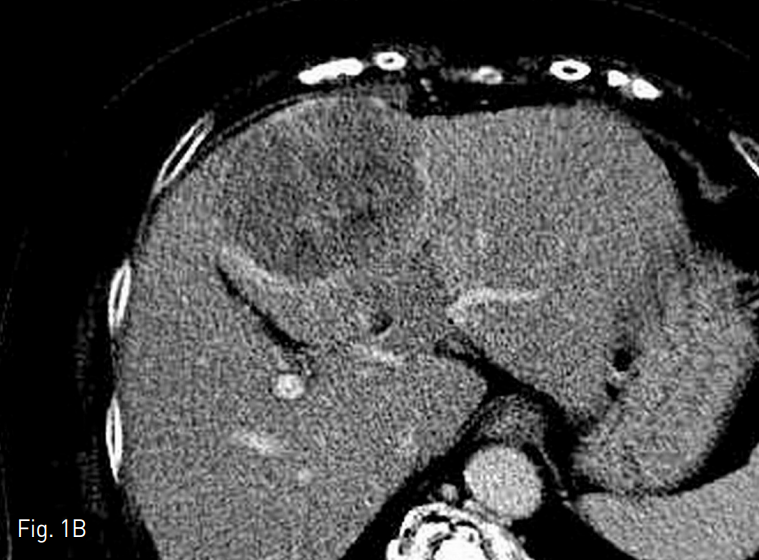

간의 4번 구역에 장경 7.5cm의 간세포암이 있었으며 (Fig. 1A), daughter nodule들이 구역 3, 4, 8번에서 각각 2cm 미만의 크기로 발견되었다. 간문맥의 umbilical portion에서 종양 혈전증이 동반되어 있었다 (Fig. 1B). 이밖에 원격 전이의 소견은 보이지 않았다.

Fig. 1. Computed tomography before transarterial radioembolization

A. There is a 7.5cm sized hepatocellular carcinoma in the liver segment 4 on arterial phase image. Three more daughter nodules are noted (not shown) in segment 3, 4, and 8.

B. There is tumor thrombosis in the um bili cal portion of portal vein on por tal phase image.